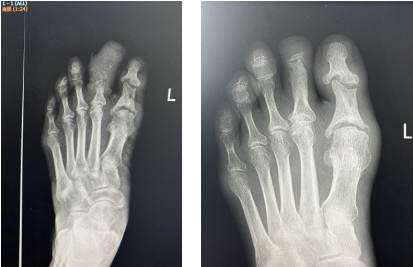

治療前后對(duì)比

3個(gè)多月后,趙阿姨回到醫(yī)院來拆掉外架,經(jīng)傷趾DR治療前后對(duì)比顯示,其左足第二趾血供明顯改善,創(chuàng)面完全愈合,傷趾還長(zhǎng)出了新指甲,與之前腫脹、糜爛的足趾判若兩“趾”。

治療前后DR對(duì)比